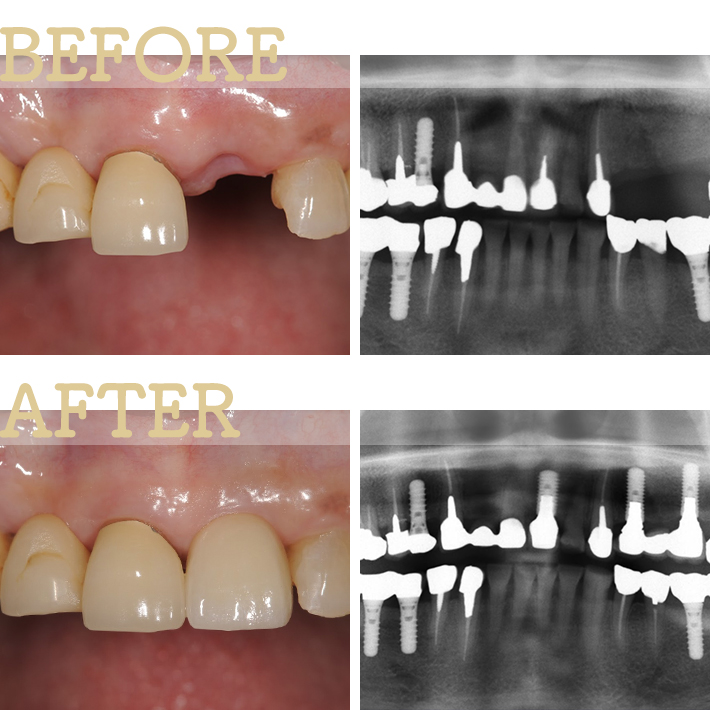

私たちが最も得意とするのが、この困難な前歯部の審美インプラントです。

まるでご自身の元々の歯であるかのように見える、

インプラントとはわからない水準で美しく仕上げることが可能です。

池田院長が実際に行った前歯部の症例をご紹介します